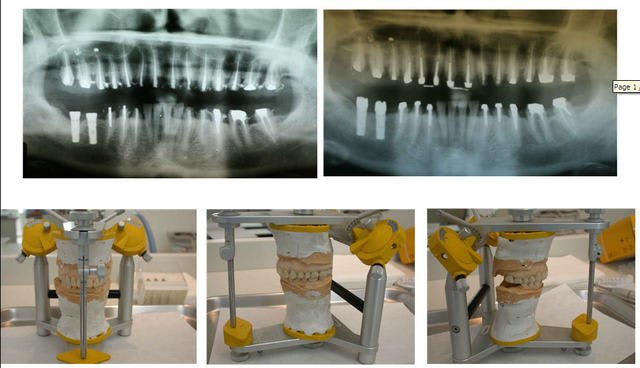

pour reparler d'occluso au niveau de ce cas :

En utilisant le SAMII j'ai essayé(et je pense quand même y être un peu arrivé je m'expliquerai après) à faire travailler cette patiente en RC.

c'ESt le montage que nous avons réalisé dès le bridge provisoire, nous ne l'avons pas monté en PIM sur l'articu puis simplement augmenté la DV sur la tige incisive pour la réalisation provisoire.

mais j'ai transféré sur l'articu la patiente en RC pour qu'en fin on obtienne PIM en RC le plus possible.

ma remarque sur le recentrage des milieux n'était pas pour faire remarquer que c'est ce que nous recherchions mais plutôt d'observer qu'en modifiant Pim en RC on avait presque obtenu ce recentrage des milieux.

si on compare photo initale en occlusion la patiente est presque en articulé croisé alors qu'avec la photo du bridge conventionnel en occlusion on a vraiment une impression d'un réel recul mandibulaire que nous n'aurions pas obtenu en augmentant de façon simple la DV sur la tige incisive et c'est pour cette raison que je pense réellement que l'on a obtenu un fonctionnement en RC.

je vais bientôt revoir cette patiente et je ferai les photos pour nous permettre de voir si les afmp sont égaux ou non.

et mes choix de formations n'ont pas été portés sur l'occlusion versus planas mais déja occlusoconscient le fait d'utilisé u articulateur semi programmable a été un premier pas vers la sagesse, mais il n'est pas rare que le prothésiste me rende la tige incisive à l'envers...(tige au maxillaire table en bas) comme sur les photos ce que personne n'a osé me dire très certainement par délicatesse...